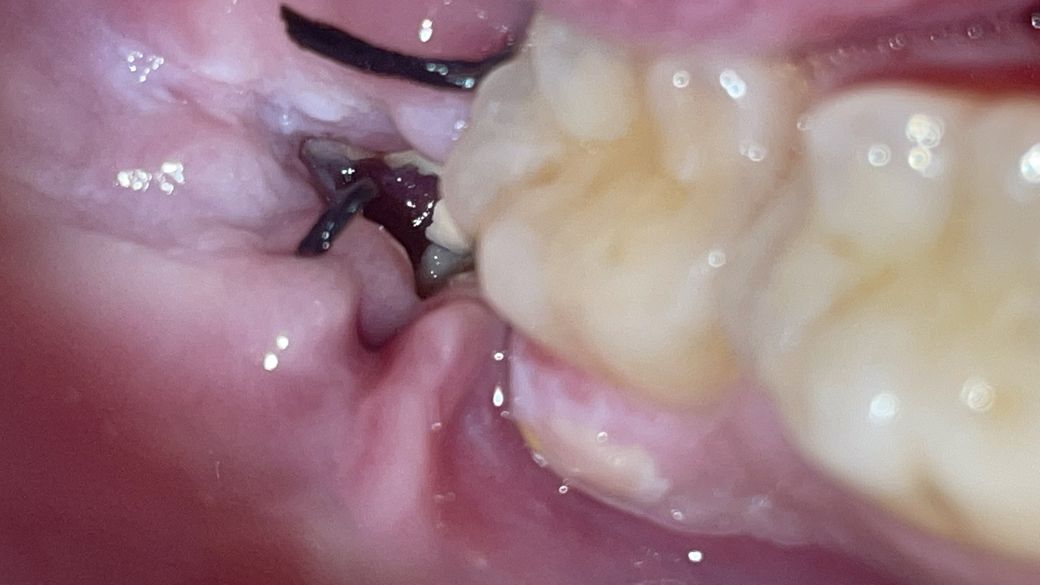

사랑니 발치부위입니다 정상적인가요?

오른쪽아래 반매복사랑니였는데

하얗게 보이는 부분이 음식찌꺼기일까요?

어제부터 보이기 시작하였는데

가글해도 빠지질 않아서 음식물이 아닌것같기도합니다

빨간부분은 혈전인가요?

사진으로만 봤을 경우에는 큰 문제가 있어보이지는 않습니다.

하지만 발치후에 형성되어야 할 혈병이 제거되어 있어서 잇몸에 아무는데 시간이 걸리고 통증이 있을수 있어요.

잇몸 주위 하얗게 보이는 것은 발치한 주위 상처가 잘 아물고 있다는 딱지로 보면 됩니다.

가운데 빨갛게 또는 약간 검게 보이는 부위는 혈병(피딱지)이 차 있는 것으로 이 혈병이 점점 잇몸조직으로

바뀌면서 상처가 아물게 됩니다.

지금 사진으로는 정확한 판단이 힘들지만 회복 정도를 보았을 때 정상적인 회복으로 보여집니다. 갑자기 급격하게 통증이 증가하는 것이 아니라면 지금의 상태는 회복 과정으로 섬유화 및 혈병이 제거되고 다음 단계로 넘어가고 있는 것으로 보여집니다.

발치 당시 매복 상태가 안 좋았다면 일주일이 지난 시점에서도 통증이 조금 남아 있을 수 있으며 시간이 지나면 대부분 회복됩니다.

하얀부분은 음식물 찌꺼기는 아닌거 같고 치유되는 과정중에 나타나는 현상입니다. 혈전은 치가굳어서 생기는 걸로 보이는 부분은 혈전은 아니고 상처부위입니다